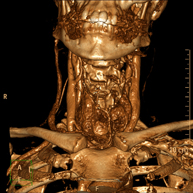

Prueba radiológica que consiste en obtener imágenes del cuello de alta definición anatómica mediante el empleo de un equipo de TC (Tomografía Computarizada). Indicaciones: estudio de tiroides, control de tumores tratados, estudio de ganglios, infecciones y abscesos. - TC Laringe

Prova radiològica que consisteix en obtenir imatges de les artèries caròtides del coll d'alta definició anatòmica, mitjançant l'ús d'un equip de TC (Tomografia Computeritzada) i la injecció de contrast intravenós. Posteriorment, es reconstrueixen les imatges en tres dimensions (3D). Indicacions: accident vascular cerebral agut, accident vascular transitori, buf cardíac. - Angio TC- aorta toràcica